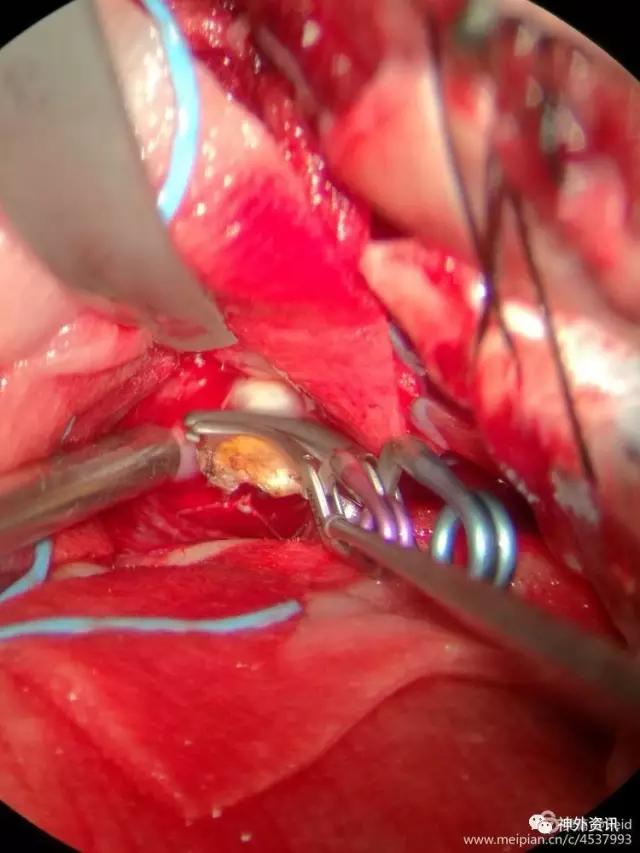

一枚动脉瘤夹夹闭动脉瘤颈后发现动脉瘤仍有供血,考虑瘤颈有血栓导致瘤颈夹闭不全。

补夹一枚动脉瘤夹,之后动脉瘤缩小,剪开动脉瘤体,证实瘤颈有局部血栓机化,瘤颈夹闭完全可靠。